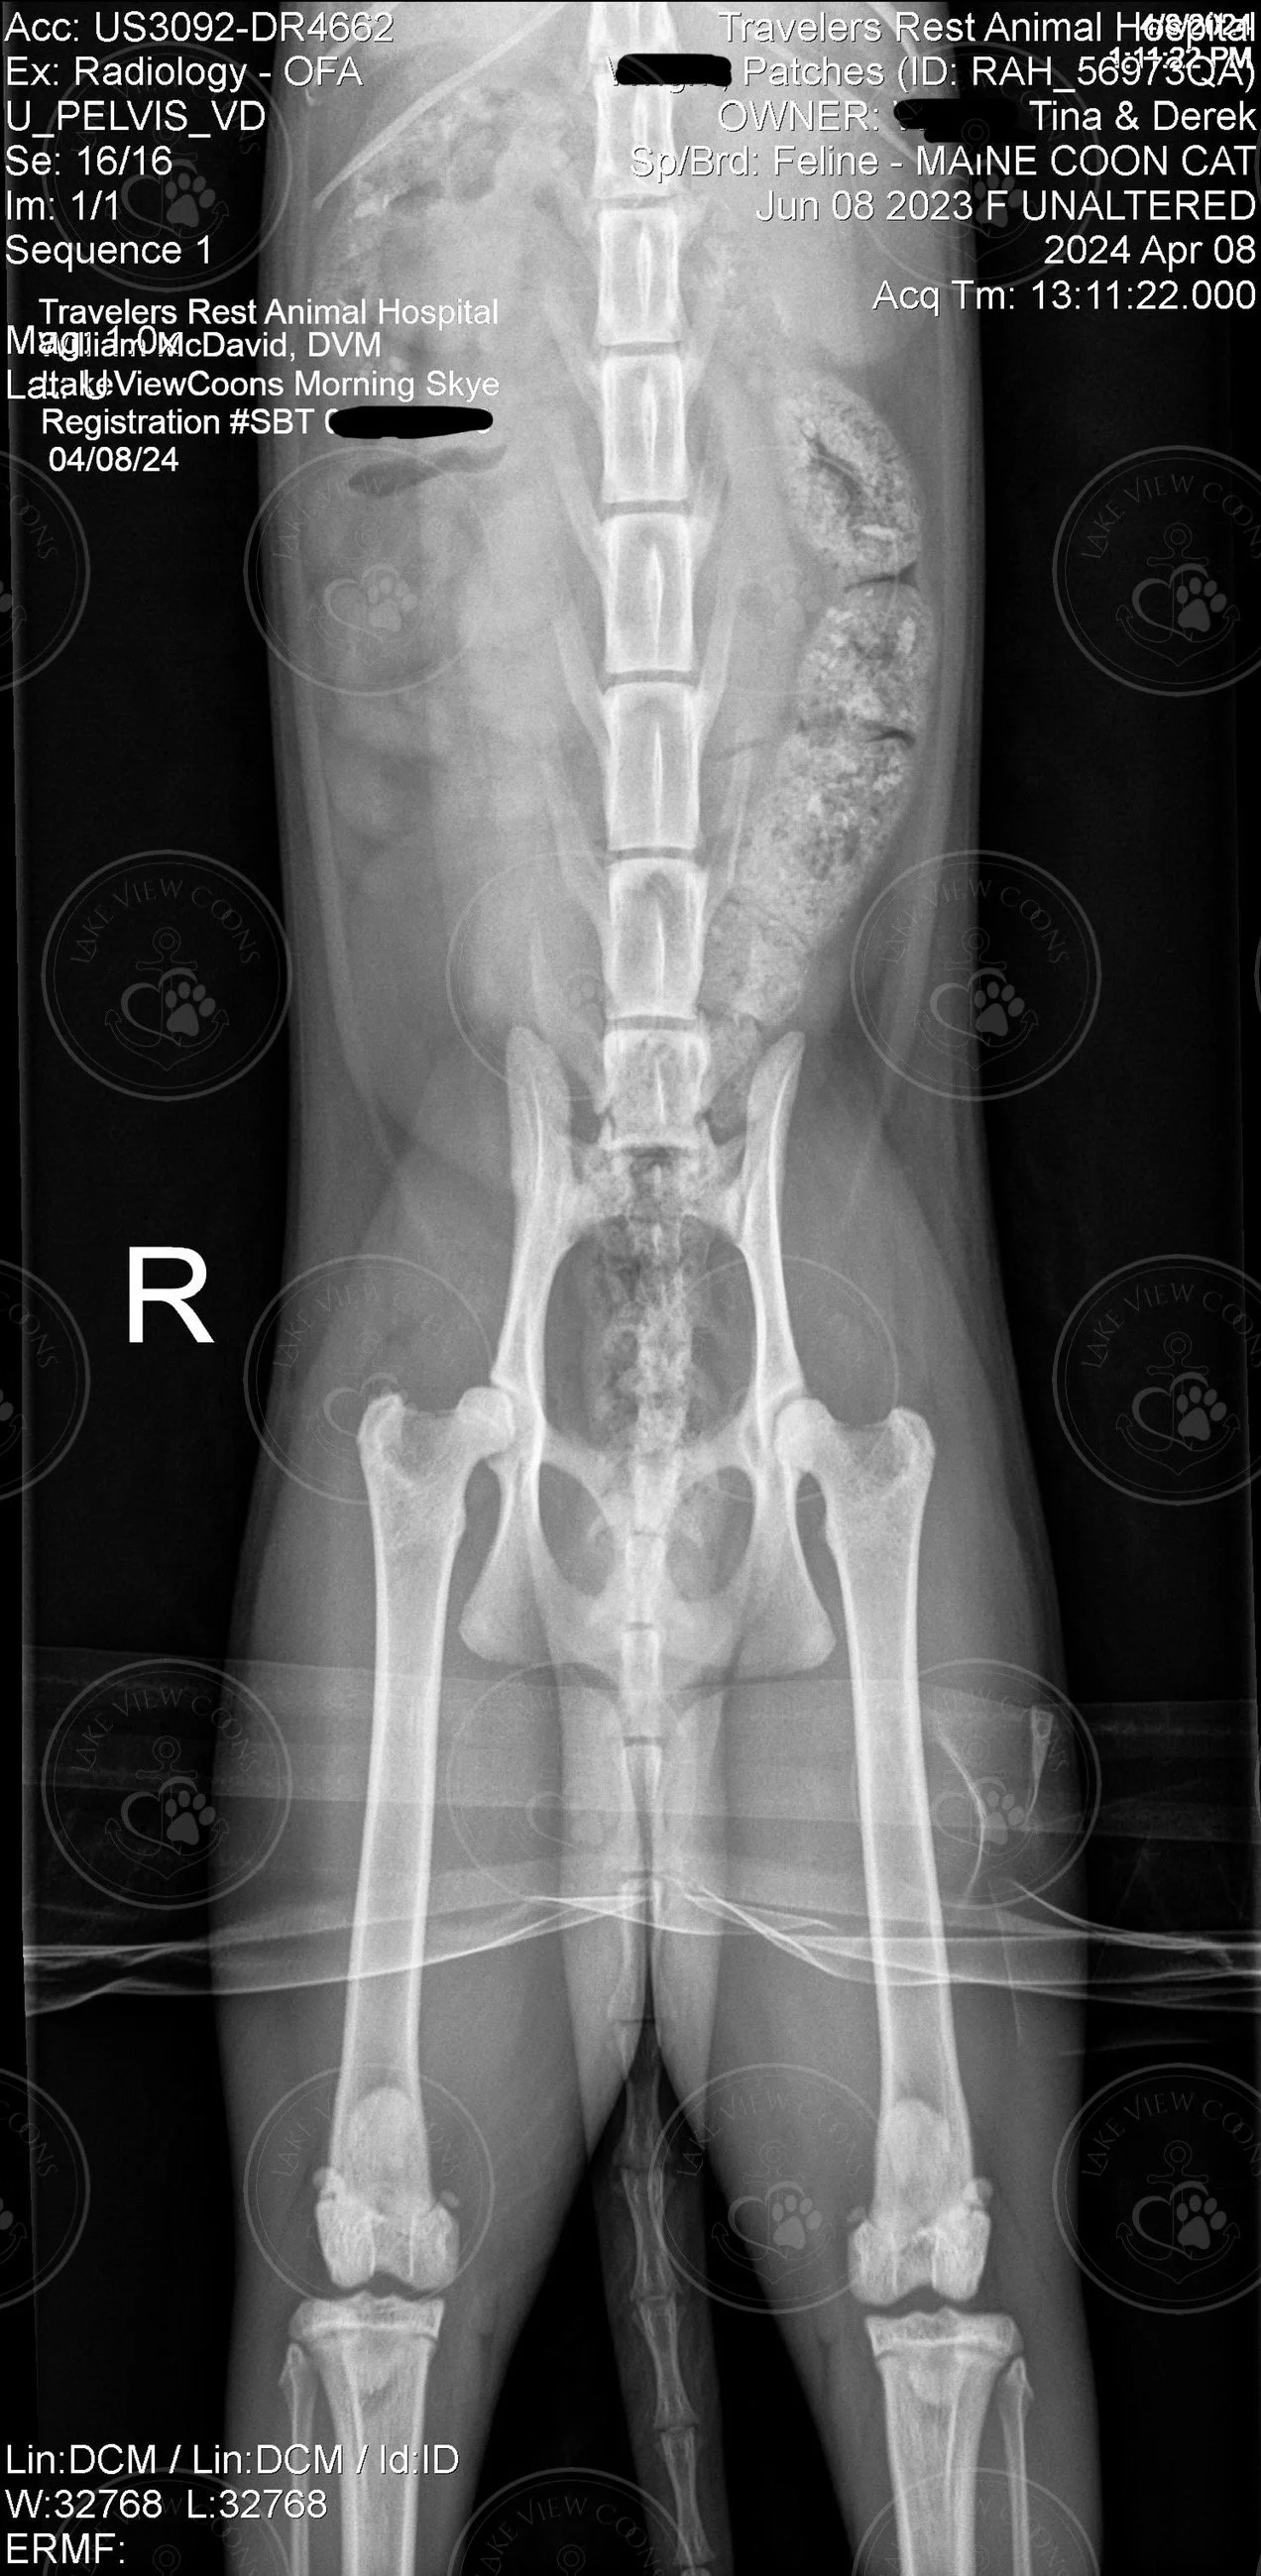

LakeViewCoons Morning Skye

Heart Echo & Hip X-Ray Results